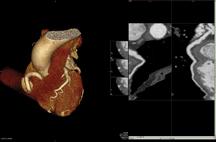

The CVDC acquired the Toshiba Aquilion ONE dynamic volume CT system to perform advanced cardiovascular CT imaging. Dr. Albert uses the Aquilion ONE for imaging of the coronary arteries because of the high image resolution of the system.

The Aquilion ONE utilizes 320 ultra-high resolution detector rows (0.5 mm in width) to image the heart in a single gantry rotation. The unparalleled result produces a 4D clinical video showing up to 16 cm of anatomical coverage, enough to capture the entire heart, and show its movement such as blood flow. The ability to image the heart in a single rotation significantly reduces radiation dose as it limits exam time and eliminates multiple exposures to radiation.

The CVDC uses Toshiba’s Vantage Atlas MR system for cardiovascular imaging without exposure to X-ray radiation. Similar to the Aquilion ONE, MR shows both anatomy and function, such as blood flow. It is used in imaging valve structure, heart function, heart attack patients and when there is heart failure for unclear reasons.